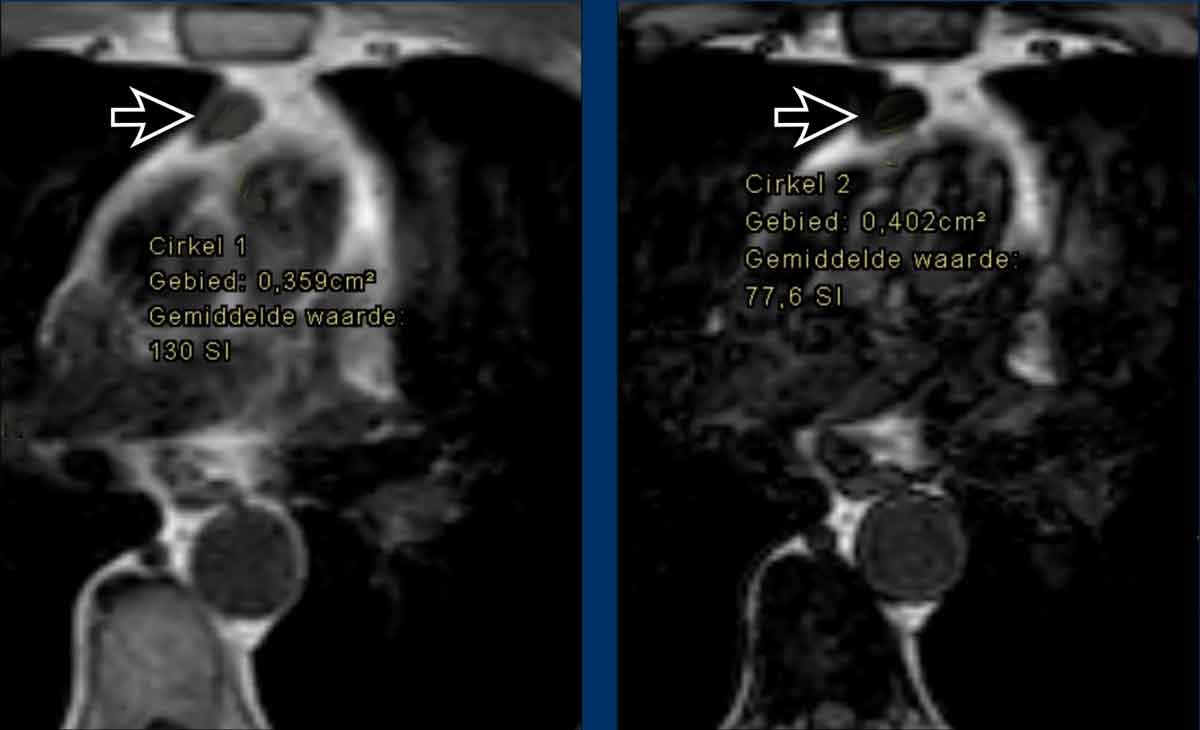

Ca lâm sàng 3

Các hình ảnh này của một phụ nữ 24 tuổi, mắc u xương (osteosarcoma) và được điều trị bằng hóa trị liệu.

Hình ảnh

Tại thời điểm bắt đầu điều trị, tuyến ức có biểu hiện tăng sản.

Tại thời điểm theo dõi 10 tháng, tuyến ức bị teo nhỏ.

Hai năm sau, xuất hiện tăng sản tuyến ức dội ngược.